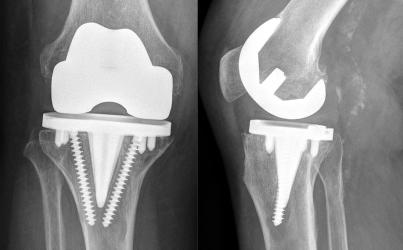

Gelenkersatz

Deutlicher Anstieg bei Knieprothesen

Endoprothesenregister meldet Rekordzahlen in der Endoprothetik.

12.11.2025 • Von O.G.